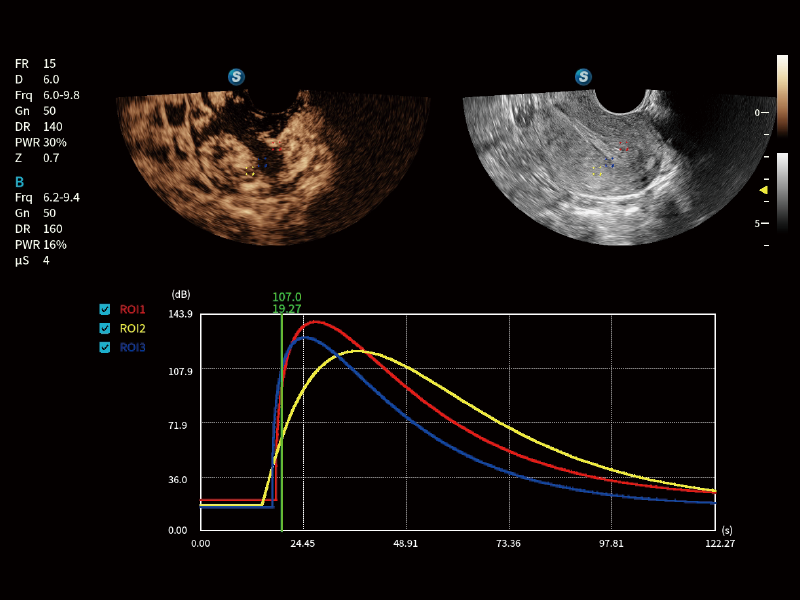

CEUS GYN